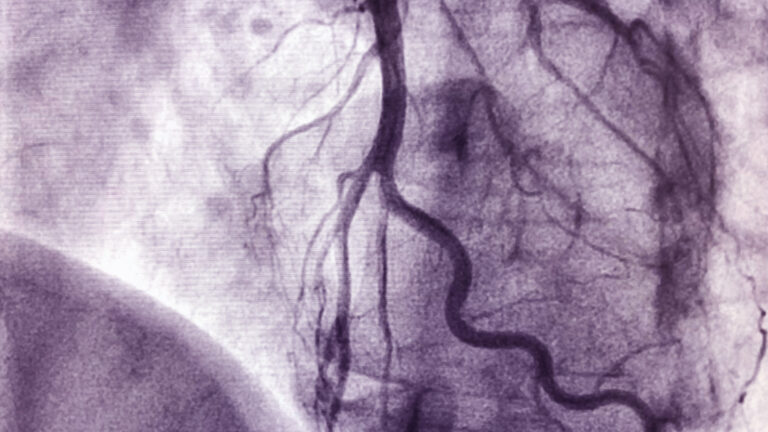

Eine Herzkatheteruntersuchung zählt zu den Routineeingriffen in der Kardiologie. Sie ermöglicht es, Durchblutungsstörungen, Herzklappenfehler oder Druckverhältnisse im Herzen präzise zu erkennen. Im Herzkatheterlabor (HKL) der Uniklinik RWTH Aachen führen die Expertinnen und Experten jährlich rund 3.000 dieser Untersuchungen durch. Mithilfe eines dünnen Kunststoffschlauchs, der vorsichtig bis zum Herzen vorgeschoben wird, überprüfen sie die Funktion und den Blutfluss des schlagenden Organs.

Der Eingriff beginnt mit einem kleinen Hautschnitt am Handgelenk oder in der Leistengegend. Über diesen Zugang schiebt das Team um Prof. Dr. med. Ertunc Altiok, Geschäftsführender Oberarzt der Klinik für Kardiologie, Angiologie und Internistische Intensivmedizin (Med. Klinik I) an der Uniklinik RWTH Aachen den Katheter in ein Blutgefäß ein und unter Röntgenkontrolle bis zum Herzen vor. Das Behandlungsteam der Sektion I Strukturelle Herzerkrankung und Interventionelle Kardiologie überwacht dabei kontinuierlich die Lage des Katheters. Über den Schlauch verabreichen sie ein Kontrastmittel, das die Gefäße und Herzkammern auf einem Bildschirm sichtbar macht und eine präzise Navigation ermöglicht.

Je nach medizinischer Fragestellung kommt entweder ein Linksherz- oder ein Rechtsherzkatheter zum Einsatz. Der häufiger verwendete Linksherzkatheter über die Arterien erlaubt die Untersuchung der linken Kammer, die das sauerstoffreiche Blut über die Aorta in den Körper pumpt. Dabei lassen sich anhand der Kranzgefäße eine beginnende koronare Herzerkrankung oder ein Infarkt diagnostizieren. Der Rechtsherzkatheter wird hingegen über die Venen eingeführt und dient der Analyse der rechten Herzkammer sowie der Lungenschlagader. Hierbei können die Herzexpertinnen und -experten Druckmessungen der Lungenarterie vornehmen und die Sauerstoffsättigung des Blutes überprüfen.